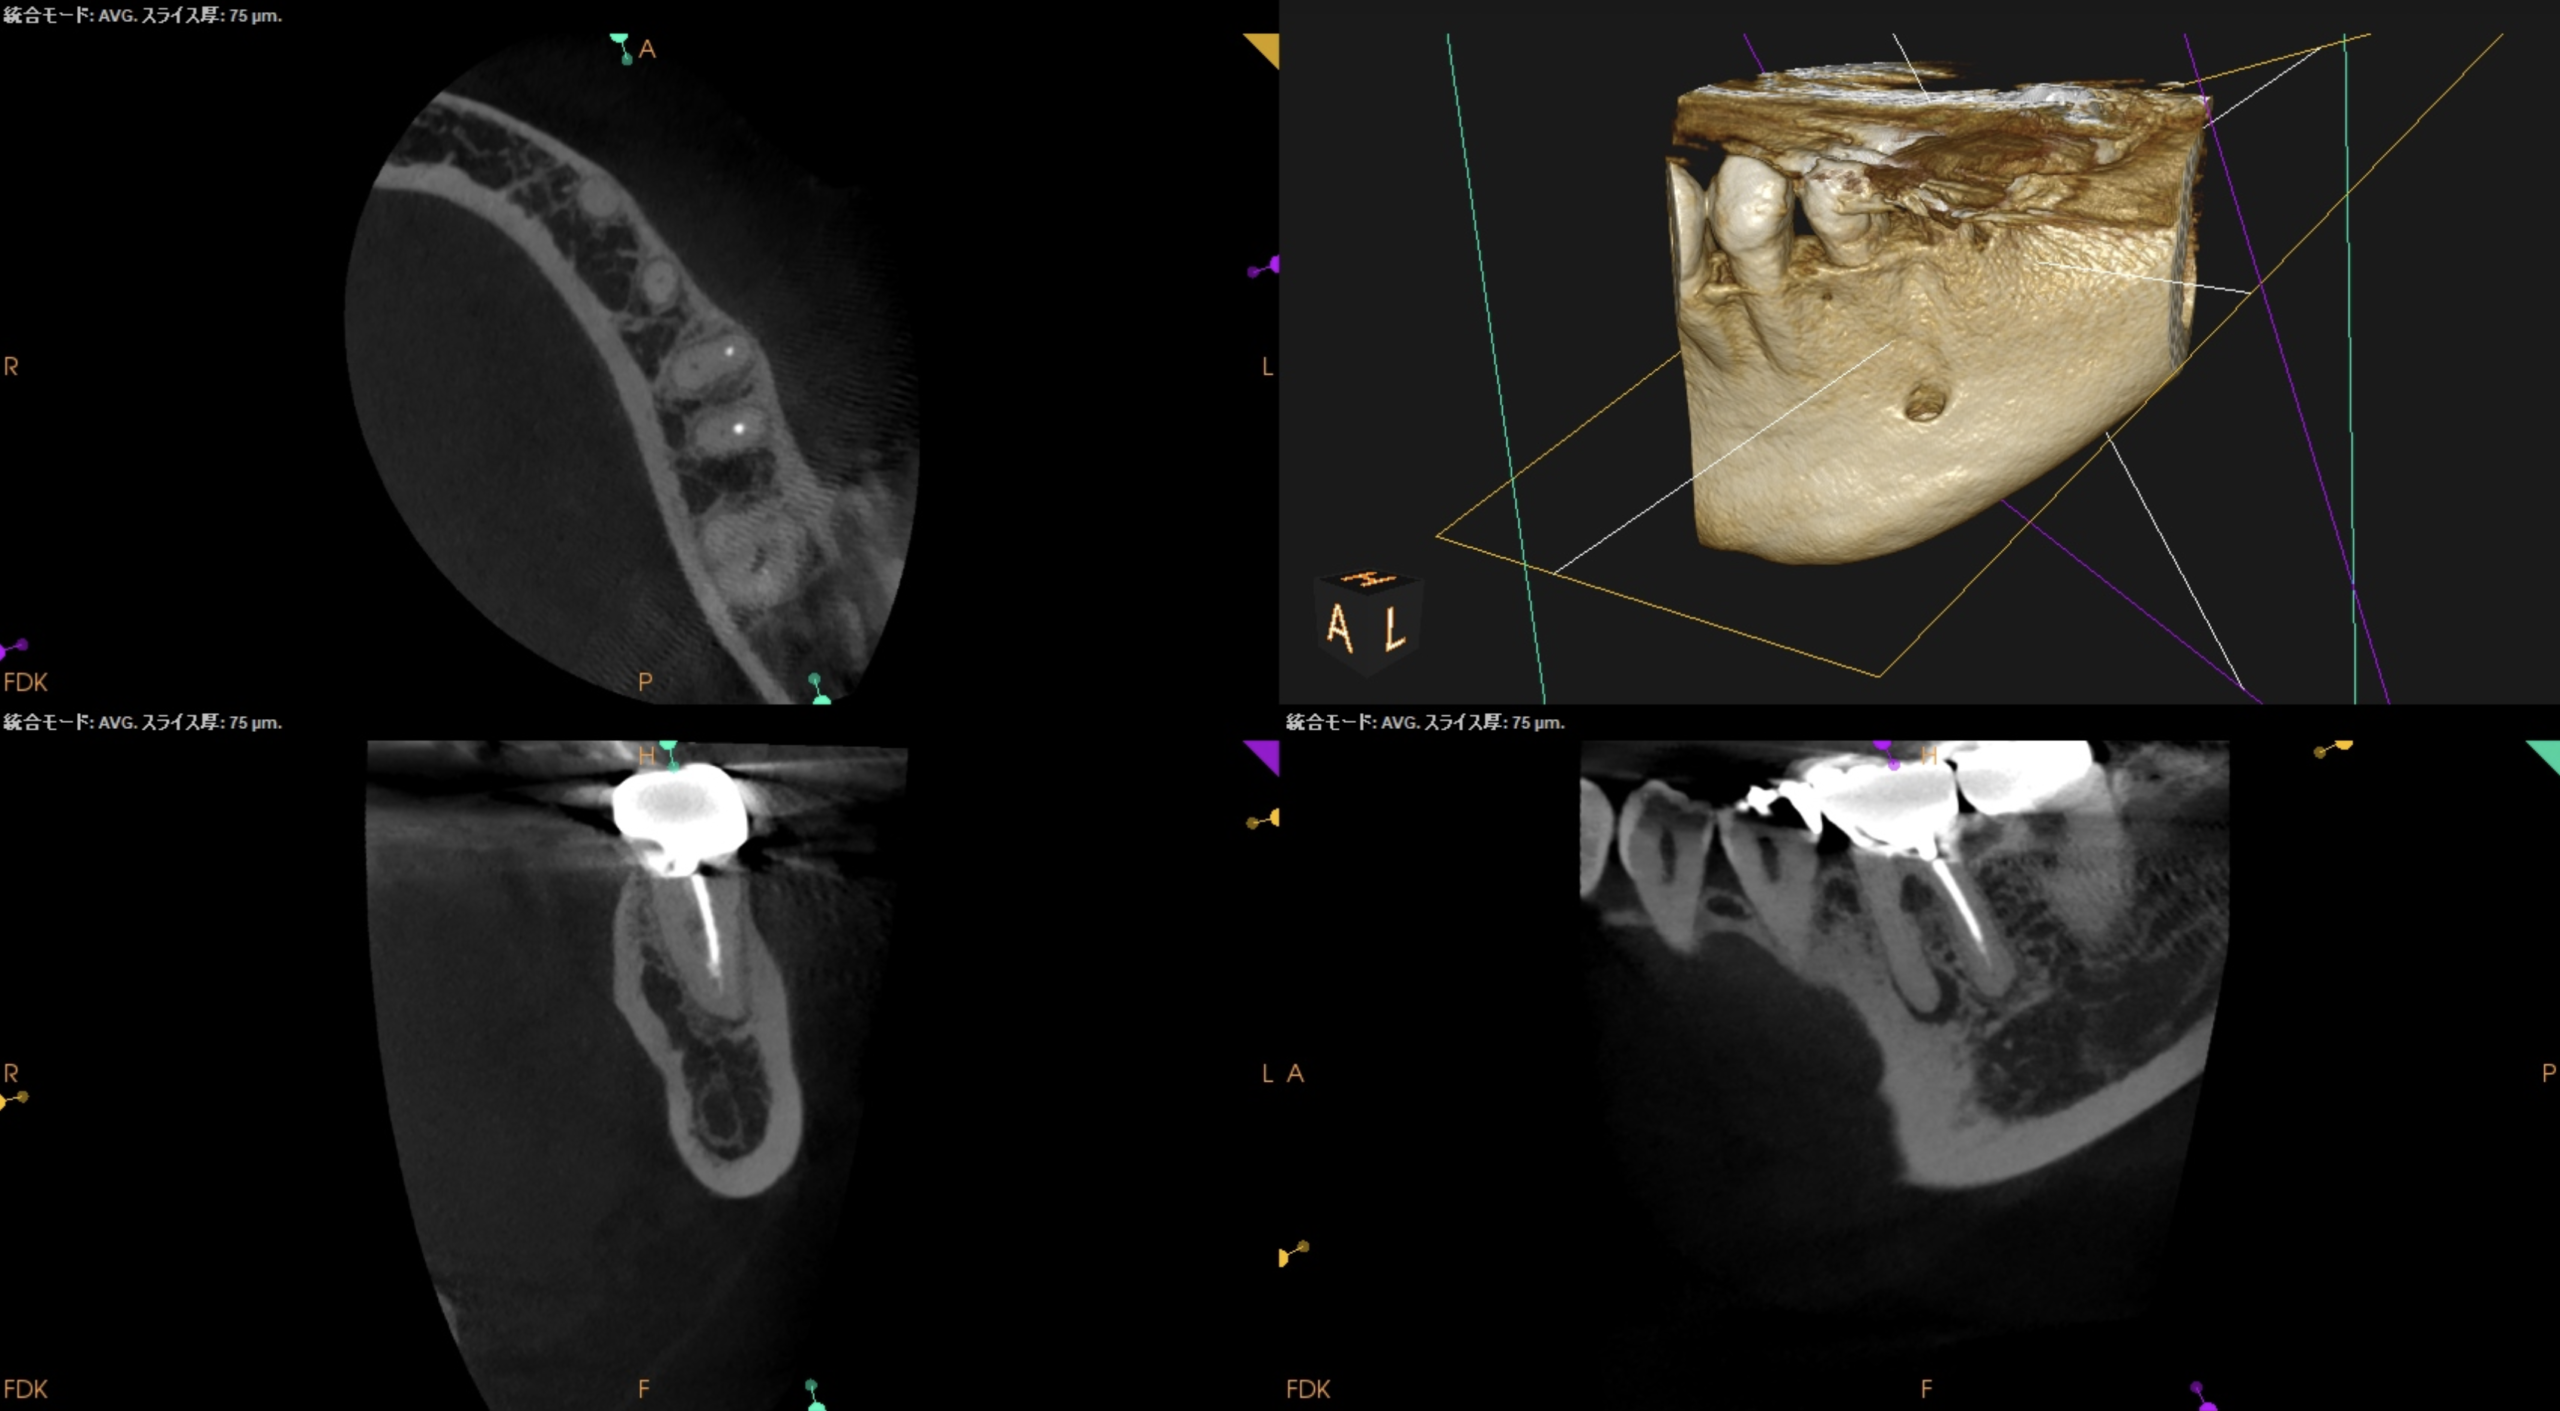

CBCTも撮影した。

CBCT(2025.10.31)

#19

MB

ML

D

一連のCBCTの絵を見ても強い圧痛を惹起させる要因が見当たらない。

ということで臨在歯の#18もCBCTを精査した。

#18

M

#18 Mのこの絵は縁下カリエスの可能性を示唆している。

明らかにCBCTの存在がなければこの存在に気づけなかっただろう。

このことからも、

もはやCBCTの存在は歯内療法においてはマストである

ということがわかる。